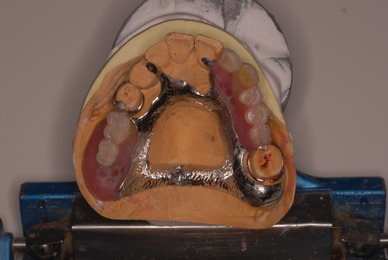

歯周病の疑いで東京のかなり遠方の方が来院されました。

驚くべきことですが、定期検診は受けていたそうです。しかしながら歯周病の指摘は受けたことがないそうです。

何故か?定期検診が虫歯のチェックのみになり、又肝心の歯周病の検査や歯周病の部分の予防や治療のためのブラシの使い方などを学んだ事がないのです。

抜いてインプラントにすれば収入は増えるでしょうし入れ歯にしても幾らかの費用はいただけるでしょう。